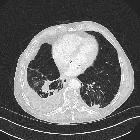

asbestos-related lung and pleural diseases as an endemic exposure in Egypt. A 56-year-old male smoker patient, working in plasters for 13 years, was diagnosed as having round atelectasis for 3 years with a latent period 10 years. Axial CT scan lung window showing left lower lobe subpleural soft tissue density with comet tail sign and underlying pleural thickening denoting round atelectasis